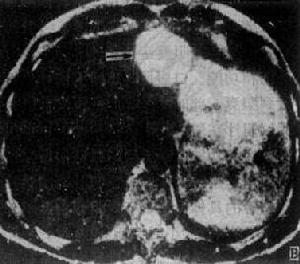

其它輔助檢查: 腹部平片顯示肝臟布滿鈣化區,類似結腸癌肝轉移。B超為回聲不均勻的多個結節;CT表現也多樣,呈多個低密度區伴周邊血管影中度增強,腫瘤內多個低血管點,有時小膽管擴張一些肝內門靜脈分支不顯影肝臟輪廓不變;血管造影顯示肝臟多個低血管腫塊